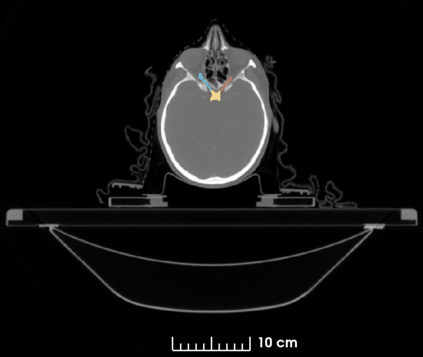

The segmentation of organs at risk (OAR) is a required precondition for the cancer treatment with image guided radiation therapy. The automation of the segmentation task is therefore of high clinical relevance. Deep Learning (DL) based medical image segmentation is currently the most successful approach, but suffers from the over-presence of the background class and the anatomically given organ size difference, which is most severe in the head and neck (HAN) area. To tackle the HAN area specific class imbalance problem we first optimize the patch-size of the currently best performing general purpose segmentation framework, the nnU-Net, based on the introduced class imbalance measurement, and second, introduce the class adaptive Dice loss to further compensate for the highly imbalanced setting. Both the patch-size and the loss function are parameters with direct influence on the class imbalance and their optimization leads to a 3\% increase of the Dice score and 22% reduction of the 95% Hausdorff distance compared to the baseline, finally reaching $0.8\pm0.15$ and $3.17\pm1.7$ mm for the segmentation of seven HAN organs using a single and simple neural network. The patch-size optimization and the class adaptive Dice loss are both simply integrable in current DL based segmentation approaches and allow to increase the performance for class imbalanced segmentation tasks.